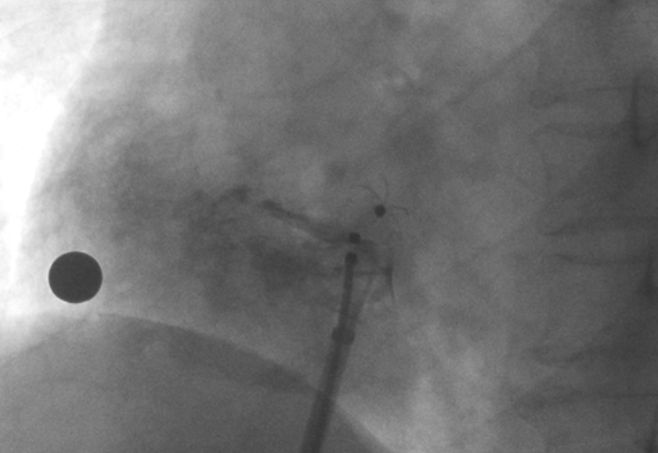

造影顯示PFO封堵完全,無殘余分流, 試驗(yàn)器械充分舒展并貼合良好

影像顯示試驗(yàn)器械適應(yīng)性貼合于房間隔兩側(cè)且穩(wěn)定